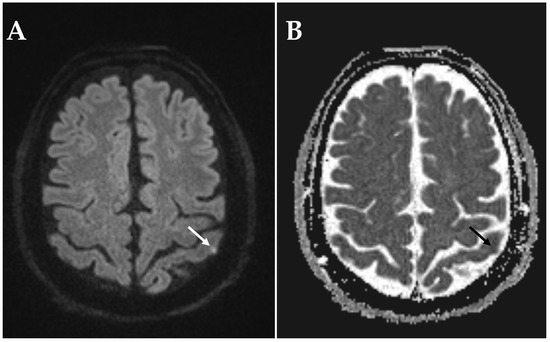

Acute Ischemic Stroke in Non-Arteritic Anterior Ischemic Optic Neuropathy

by Victor Wenzel, Leon Alexander Danyel, Sophia Meidinger, Eberhard Siebert, Theresia Knoche and Charlotte Pietrock

Diagnostics 2025, 15(24), 3192; https://doi.org/10.3390/diagnostics15243192 - 14 Dec 2025

Background: Non-arteritic anterior ischemic optic neuropathy (NAION) is a neuroophthalmological disorder characterized by impaired blood flow to the optic nerve head. There is uncertainty about whether, in some cases, NAION may be caused by proximal embolism of the posterior ciliary arteries. Diffusion-weighted magnetic [...] Read more.

Background: Non-arteritic anterior ischemic optic neuropathy (NAION) is a neuroophthalmological disorder characterized by impaired blood flow to the optic nerve head. There is uncertainty about whether, in some cases, NAION may be caused by proximal embolism of the posterior ciliary arteries. Diffusion-weighted magnetic resonance imaging (DWI-MRI) can provide evidence of concurrent cerebral infarction that may indicate a common embolic etiology. Methods: Adults with ophthalmological diagnosis of NAION who underwent cerebral DWI-MRI within 14 days from onset of visual impairment were included in a retrospective cohort study (2013–2021). DWI-MRI images were assessed for presence, location, and type of ischemic stroke by a board-certified neuroradiologist blinded for clinical patient data. Results: Among 122 patients (mean age 64.6 ± 11.9 years), DWI-MRI indicated acute/subacute ischemic stroke in three cases (2.5%), all located within the anterior circulation in the territory of the left middle cerebral artery and ipsilateral to the affected eye in two cases (1.6%). Ischemic stroke location was cortical in one case (0.8%) and subcortical in two cases (1.6%). Acute ischemic stroke indicated by a hyperintense DWI signal and corresponding low ADC was present in one patient (0.8%). Two patients (1.6%) had subacute ischemic stroke (hyperintense DWI signal and normal or elevated ADC signal). Only one NAION patient (0.8%) had acute embolic stroke corresponding to the vascular territory of the affected eye. Conclusions: Concurrent embolic ischemic stroke in NAION is exceedingly rare. Our findings support the prevailing pathophysiological theory of NAION as a non-embolic disease. Full article

Show Figures

Figure 1